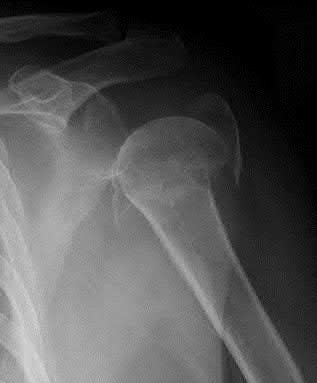

A 64-year-old woman is thrown off a horse, sustaining the injury shown in Figures A and B. She undergoes surgical fixation as seen in Figures C through E. What is the most commonly reported complication of this procedure?

The patient in the scenario has a 2-part proximal humerus fracture treated with a locking plate as seen in Figures A-E. The most common complication with the use of this implant is screw penetration. The terms screw cut out and penetration are often used interchangeably in the literature with cut out appearing more frequently in reports regarding intertrochanteric fractures.

Owsley et al retrospectively reviewed 53 proximal humerus fractures treated with locking plates and the same post-operative protocol. The most common complication was screw cut out or penetration, followed by varus displacement. They concluded that 3 and 4-part fractures in patients over 60 years have a higher incidence of failure.

Agudelo et al retrospectively reviewed 153 patients at a level-one trauma center treated with proximal humerus locking plates, investigating modes of failure for the implant. They determined that varus malreduction (head-shaft angle